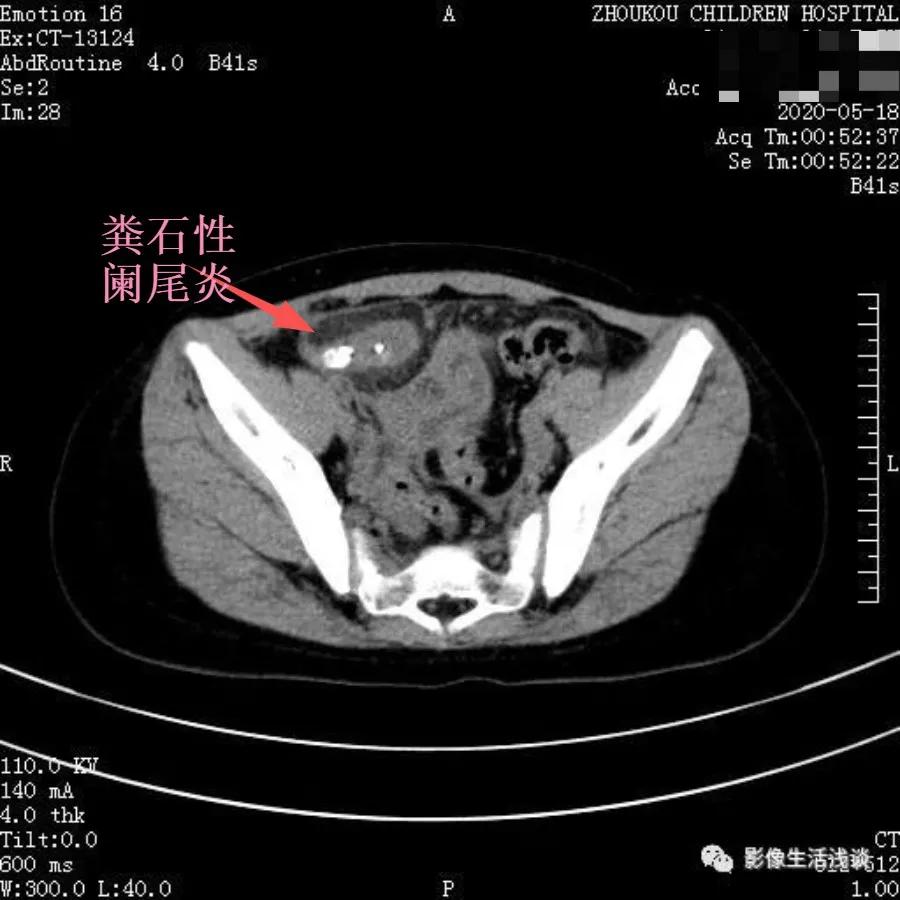

下图是我们工作中常见阑尾炎病例